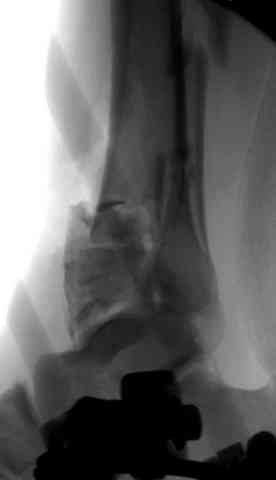

Здесь выставлена пара случаев перелома пилона, оба

случая леченные этапным наружным фиксатором.

Второй случай фиксирован аппаратом Илизарова.

Открыто или закрыто - это уже зависит от опыта и

наличия материала. Минимальным аппаратом Илизарова или одним из Contoured Medial или Antero-Lateral Locking Plate из лимитирванного доступа не имеет значения, но самое главное необходимо добиться репозиции сустава.

Первичная пластина или интрамедуллярный фиксатор на малоберцовую зависит от характера перелома, косые и многооскольчатые пластинами, а поперечных можно интрамедуллярными фиксаторами. Восстановленная длина малоберцовой служит ориентиром и помогает определению высоты большеберцовой во время восстановления.